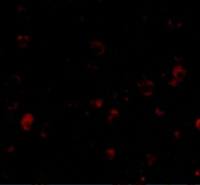

IHC-Fr analysis of mouse DRG tissue using GTX16610 VRL1 antibody.

Panel A : TRPV2 (green) appears in patches along the perimeter of the DRG (arrows).

Panel B : Neurons containing neurofilament 200 (red) are scattered in the DRG, also in patches (arrows).

Panel C : Merge of the two panels shows that the spatial distribution of neurofilament 200 and TRPV2 expression overlaps. However, DRGs showing robust expression of neurofilament 200 do not contain TRPV2.